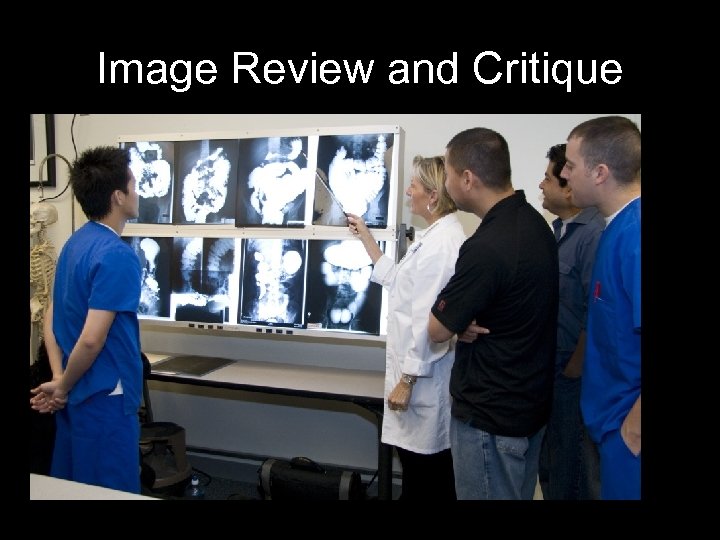

Image Review and Critique

Image Review and Critique